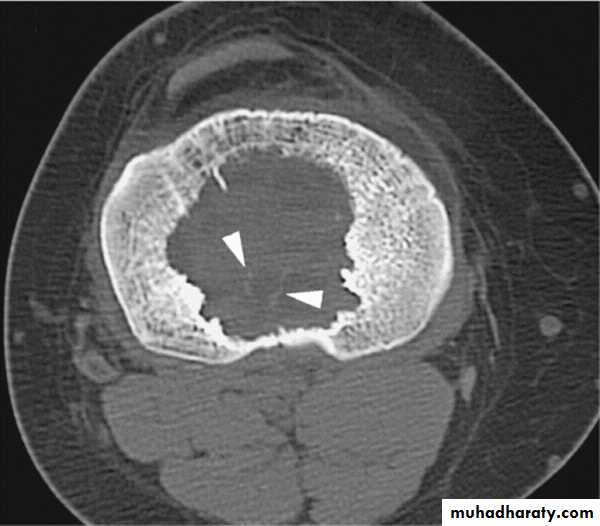

CT SCAN